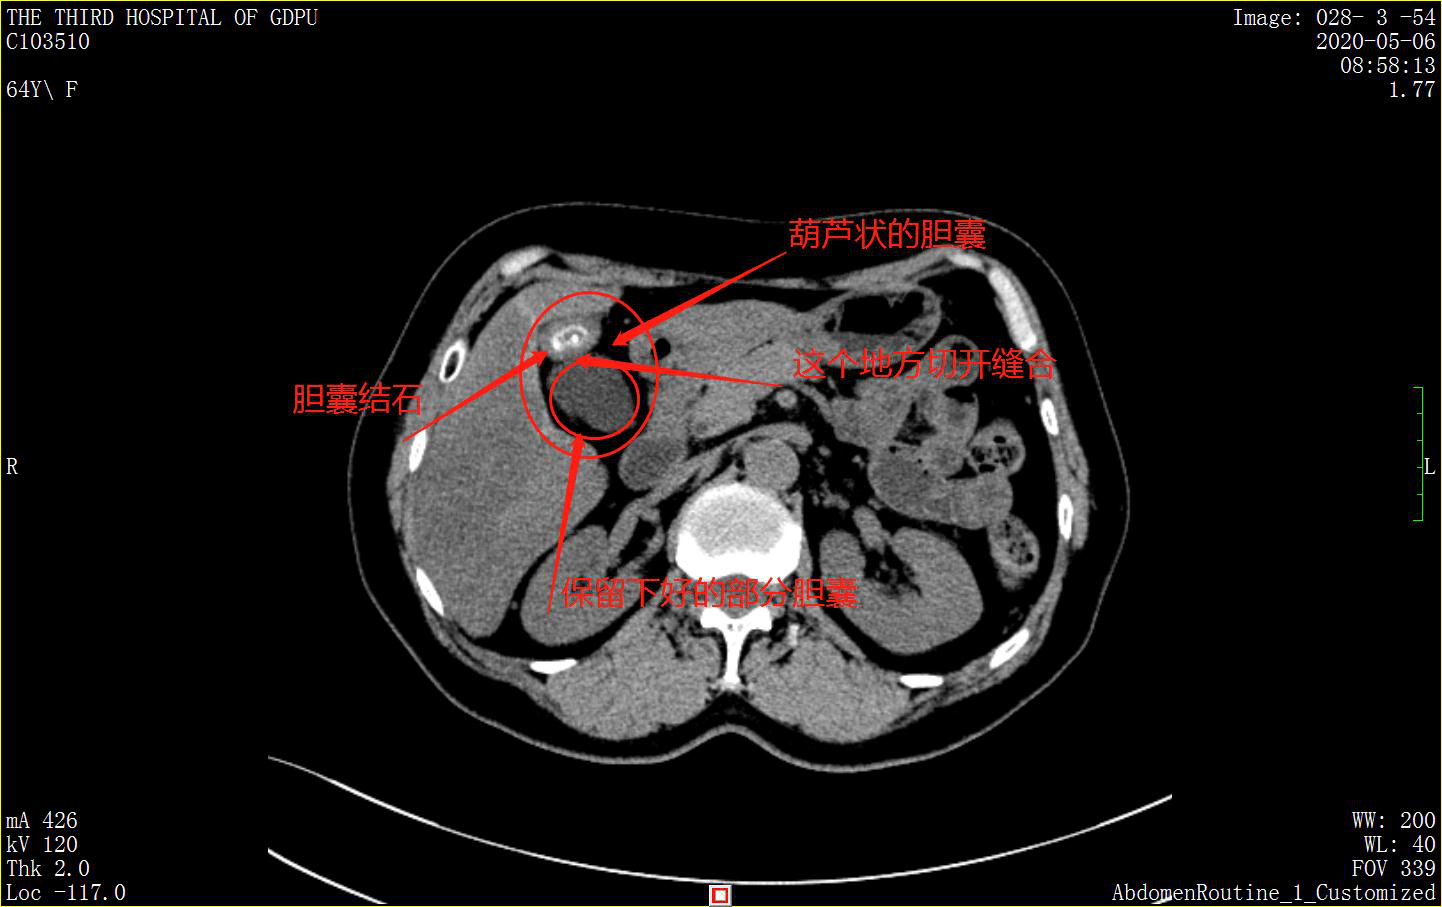

5月5日患者就诊并收治入院。入院后进一步做检查,发现该患者不是单纯的胆囊结石伴慢性胆囊炎,而是胆囊局限性腺肌症,也就是胆囊呈“葫芦”状的原因。那么什么是胆囊腺肌症?主诊医生梁法生博士解释道:胆囊腺肌病是一种以腺体和肌层增生为特征的良性胆囊疾病,为胆囊增生性疾病的一种,以慢性增生为主。胆囊腺肌增生会形成粘膜内憩室,也就是“葫芦”状的较小一头,看似像胆囊底部又长出来另一个小胆囊,囊的形态不一,可呈圆形、卵圆形或不规则形。这个增生的胆囊不能正常收缩,很容易淤积,继发感染,形成结石。这就是该患者胆囊结石形成的本质原因。

根据患者的实际情况,因为胆囊局限性腺肌症,结石恰好在“葫芦”较小的一头,也就是在增生的囊内,因此主诊医生梁法生博士解释,该患者产生结石的原因,其实就是胆囊局限性腺肌症,胆囊收缩和分泌不通畅,很容易产生淤积,进而形成结石。因此该患者的手术,选择了胆囊部分切除,即切除增生的部分胆囊,保留完好的部分胆囊。这样同时去除了结石和增生的胆囊,清除了形成结石的温床,实现了对因治疗,从而大大降低了胆囊结石的复发。